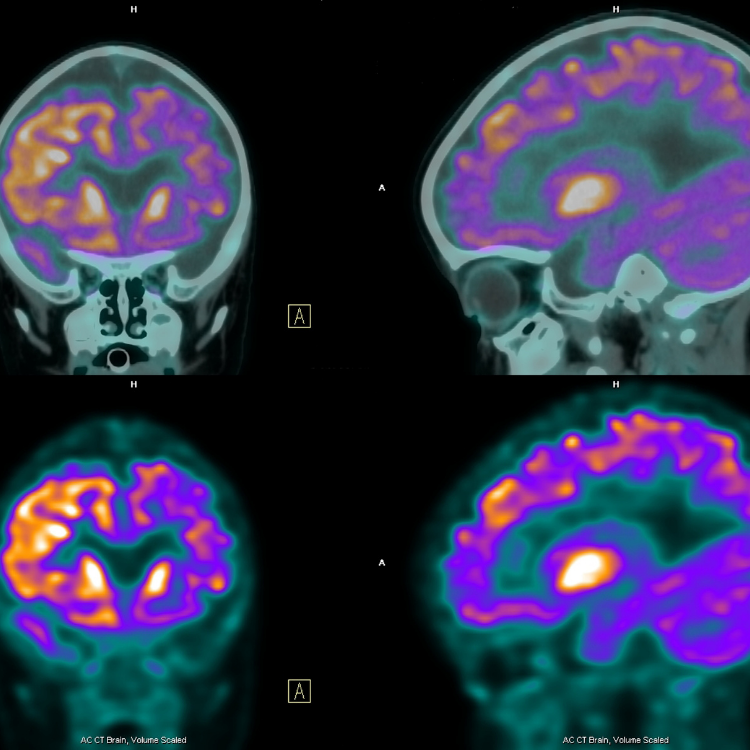

Pet:

Organ ve dokuların fonksiyon ve metabolizmalarındaki değişiklikleri anatomik detaylarla birlikte gösteren, etkinliği kanıtlanmış bir Nükleer Tıp görüntüleme tekniğidir. Özellikle onkolojide tümörün saptanması, derecesinin belirlenmesi (evreleme), tedaviye yanıtın değerlendirilmesi, nüks/metastaz şüphesi ve tümör belirteçlerinde yükselmesi durumunda yeniden evreleme, radyoterapi planlaması ve bazı durumlarda mevcut olan kitlenin iyi yâda kötü huylu olup olmadığının tespit edilmesinde kullanılan en ileri medikal görüntüleme tekniğidir. Bu yöntemde; • Bir şeker türevi olan glikozun pozitron tipi ışıma yapan radyoaktif madde (Flor–18) ile işaretlenmiş molekülü (F–18- FDG) hastaya damar yolundan uygulanır. • Belli bir süre verilen radyoaktif maddenin tüm vücuda yayılması ve ilgili dokularda tutulması için beklenir (yaklaşık 45–60 dakika). • Kamera altına alınan hastanın, toplam 12-20 dk süre içerisinde, tüm vücut bilgisayarlı tomografi ve pozitron emisyon tomografi (PET) görüntüleri üç boyutlu olarak elde edilir. • Organ ve dokulardaki normal ve normal dışı metabolik fonksiyon gösteren patolojik alanların üç boyutlu görüntülenmesi sağlanır. *Günümüzde gelişmiş ülkelerde kanserden ölüm oranı tüm ölüm sebepleri arasında ikinci sıradadır. Bunun da ilk sırasında akciğer kanserleri yer almaktadır. *Kanser tedavisinin başarısında en önemli etken ERKEN TANI ve DOĞRU EVRELEME yani vücuda yayılımının tespitidir. *Kanser yayılımının doğru ve erken olarak belirlenmesi tedavi kararını etkilemekte ve sağ kalım oranını arttırmaktadır. PET çalışmaları metabolik değişiklikleri gösterdiği için lezyon hakkında diğer görüntüleme yöntemlerinden çok daha erken bilgi vermekte, BT ile de anatomik lokalizasyon ve detay gösterildiğinden PET-BT çalışmaları hastalığın erken tanısına ve doğru evrelendirilmesine önemli katkı sağlamaktadır. olmaktadır.